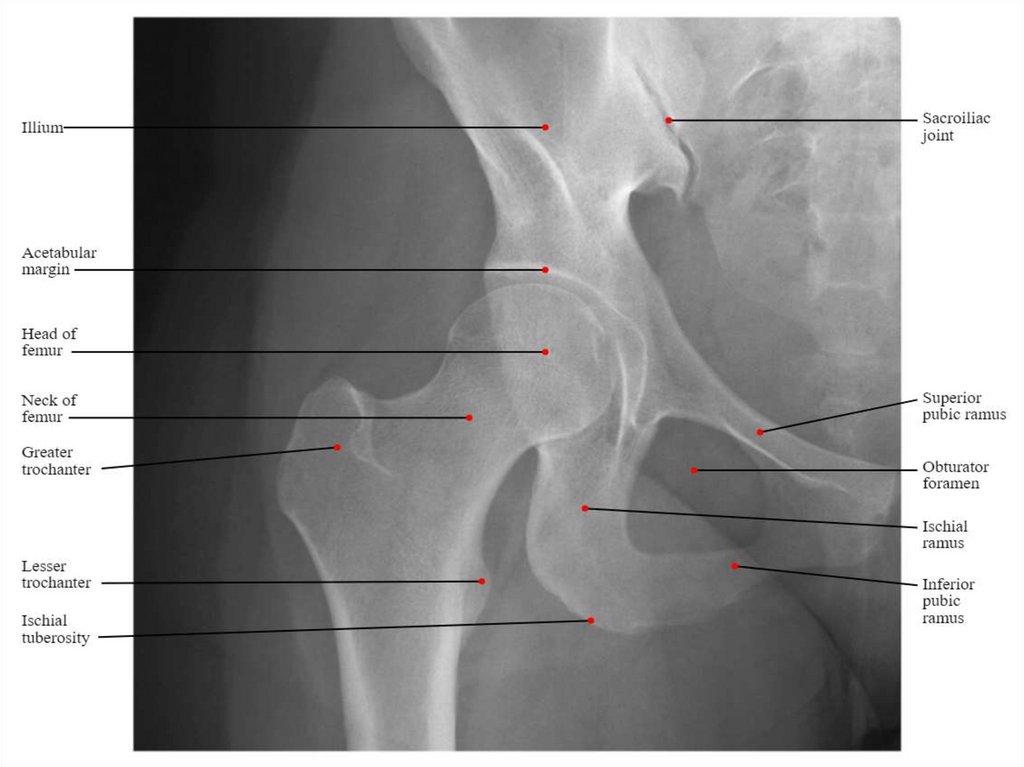

У тій ділянці, де тіла усіх трьох кісток зростаються, утворюється

кульшова западина, яка має:

- півмісяцеву поверхню,

- ямку кульшової западини,

- кант кульшової западини

(край кульшової западини);

- вирізку кульшової

западини.

Кульшова кістка має

затульний отвір та

велику сідничну

вирізку.